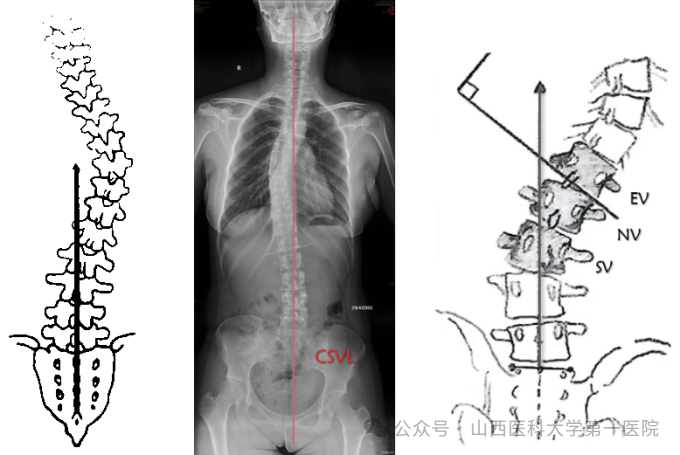

2. 顶椎(APEX)

顶椎是评估脊柱畸形的常用指标,对手术策略制定具有重要指导意义,具有如下特点:顶椎是偏离骶骨中垂线(CSVL)最远的椎体;顶椎可以是椎体也可以是椎间盘;顶椎在横断面上旋转程度最大。

3. 骶骨中心垂直线(CSVL)

从S1上缘中点垂直于地面绘制的垂线,它描绘了脊柱相对于骨盆的冠状位置。